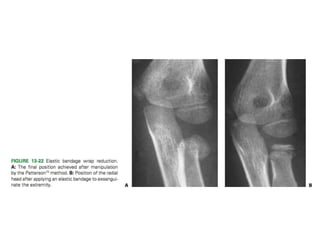

Closed Reduction Techniques

• Patterson’s manipulative technique.

• Kaufman et al. technique - elbow is manipulated in the flexed position.

• Neher and Torch reduction technique

• The Israeli technique.

• Esmarch bandage wrap technique - as an adjunct to all techniques. Helps in easy reduction.

• Monson technique - proximal fragment should be held by annular ligament. Radius shaft is

reduced.

• Radial neck angulation should be reduced to less than 45 degrees in children under 10 years

of age and less than 30 degrees in children greater than 10 years of age.

• The radiocapitellar joint should be congruent.

• The elbow joint must be stable to stress.

• Early range of motion should be encouraged once the acute pain has resolved, generally